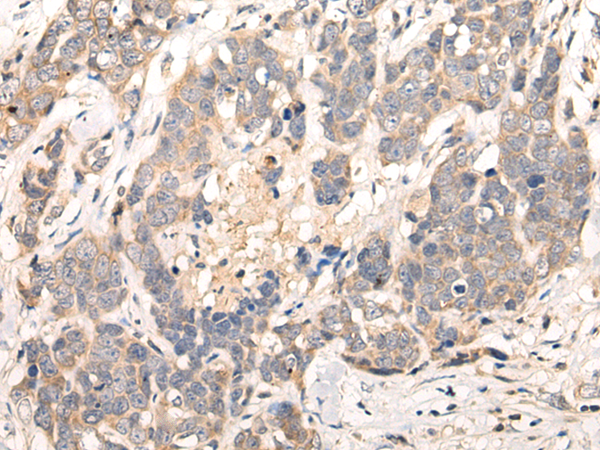

ELISA, IHC

IHC positive control:

Human thyroid cancer and human ovarian cancer

IHC Recommend dilution:

10-50